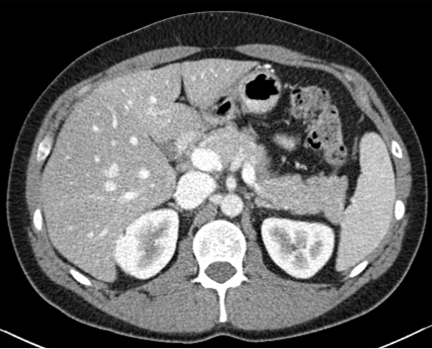

Figure 2: Comparison of generated Pseudo-LDCT images and their noise. (a) LDCT, (b) Random noise histogram, (c) Gaussian noise, (d) Ours. The right-bottom patch indicates the noise lying on each image. The noise quality of (b) and (c) shows that random noise cannot represent (a). In contrast, (d) shows almost similar to (a)

For evaluation, the 2016 AAPM Low-Dose CT Grand Challenge dataset[16] was used and split into 3 train and 7 test, respectively. It consists of abdominal LDCT and NDCT images obtained from 10 patients with image size 512×512512512512\times 512. The voxel space of CT images is 0.5mm×0.5mm0.5𝑚𝑚0.5𝑚𝑚0.5mm\times 0.5mm with 3mm3𝑚𝑚3mm slice thickness. To demonstrate that our method works with any existing learning method, we applied our method to N2C (Noise2Clean), N2N (Noise2Noise)[13], and N2V (Noise2Void)[11]. N2C is a supervised learning method that uses all available labeled paired data. N2N and N2V are self-supervised learning methods which use noisy pair images and masking schemes. Also, to demonstrate the effectiveness of our noise model, we compared LDCT denoising performance against existing noise generation techniques i.e. Random Noise histogram (Hist), Gaussian noise (Gaussian), and Single noise model++Noise histogram (Model+Hist). Hist samples noise from the difference map based on the histogram between LDCT and NDCT images, whereas gaussian samples the noise from a Gaussian distribution with zero mean and 0.02 standard deviation. Model+Hist is the combination of a single pre-trained LDCT noise model (using all subjects in the training dataset) and Hist. For evaluation, Peak Signal-to-Noise Ratio (PSNR) and Structural Similarity (SSIM) are reported.

Figure 3: Comparison of existing methods and Ours. (a) LDCT, (b) N2C, (c) N2N, (d) N2V, (e) NDCT, (f) N2C+Ours, (g) N2N+Ours, (h) N2V+Ours.

For parameter updates, it is crucial to generate high-quality Pseudo-LDCT images i.e. images similar to an actual LDCT image. If high-quality Pseudo-LDCT images are provided to the model for training, CT denoising performance can be improved. In contrast, using low-quality Pseudo-CT images may adversely affects the model learning, and consequently lead to decreased denoising performance. Table. 1 also shows the average PSNR and SSIM in different Pseudo-CT image generation settings. Here, both Hist and Gaussian reported lower performance compared to N2C. Based on our observations, this serves to show that random noise employed in natural images is not useful for CT denoising. In contrast, when our noise model was combined with Hist i.e. Model+Hist, performance gains over N2C were noted. This implies that our noise model can generate reasonable noise similar to the actual CT noise, and also improves performance. Furthermore, our ensemble noise models without parameter update show improved results over Model+Hist without the need for additional random noise.

In Figures 2 and 3, we show comparison results of Pseudo-LDCT images and their generated noise using various methods, as well as the predictions of our method for each. In Fig. 2, Pseudo-LDCT images and their noise with Hist and Gaussian highlight a huge discrepancy between the actual LDCT image and its noise. In the case of random noise that is shown to be independently distributed across the entire image, it is often useful for natural image denoising. Moreover, this types of noise does not accurately reflect the nature of CT images. Through the proposed method, we show it is possible to generate Pseudo-CT images that preserve overall CT image characteristics with high quality (Fig. 3).